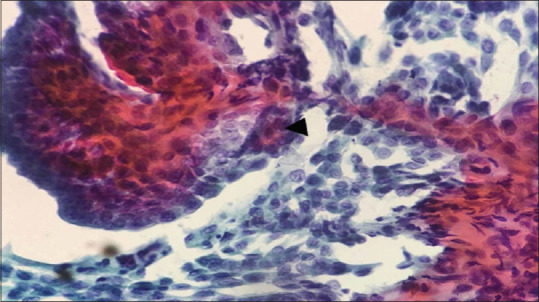

Background: Aspiration cytology is one of the first-line diagnostic tests in thyroid malignancies. Fine-needle aspiration cytology (FNAC) in thyroid lesions causes hemorrhagic smear and cell trauma, often leading to the repetition of smear and delay in diagnosis. This study was conducted to identify the diagnostically superior technique with regard to thyroid swelling and to assess the quality of smears obtained from FNAC and fine-needle nonaspiration cytology (FNNAC).

Methodology: This was a prospective diagnostic study carried out for 2 years in a tertiary care center from South India. All patients with complaints of thyroid swellings, after examination, underwent FNNAC, followed by FNAC of the lesion. They underwent thyroidectomy when indicated. The final postoperative biopsy reports were compared with the preoperative reports of these two techniques (FNNAC and FNAC). The quality of smears was compared using Mair's score.

Results: The sensitivity, specificity, positive predictive value, negative predictive value, and accuracy in diagnosing malignancy were 93.4%, 100%, 100%, 98.78%, and 98.96% for FNNAC and 94.12%, 100%, 100%, 98.82%, and 99% for FNAC, respectively, which were comparable. Regarding the quality of smears, FNNAC had more smears with less blood in the background. FNAC had more smears with adequate cellularity. The difference in overall Mair's score between the two techniques was not significant (P = 0.28).

Conclusion: No difference was found in the accuracy of FNAC and FNNAC in diagnosing thyroid lesions. Furthermore, the smear quality of both techniques was comparable. Hence, either can be used based on the operator's preference and experience.